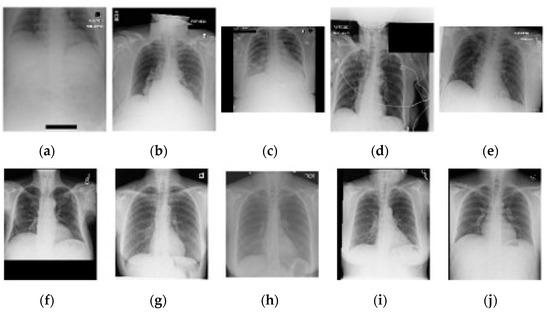

Figure 4. A selection of five random AP (ae) and PA (fj) chest images from the complete included dataset. Note the difference in image quality related to exposure, orientation, and cropping between AP and PA positioning.

Supplementary information related to image quality was obtained using a cursory inspection of 100 random PA and AP images, of which some representative examples are shown in Figure 4. A deviation in average image quality related to image acquisition was visible in 15 PA cases and 52 AP cases. The largest deviations appear on AP images and are related to inspiration, field size, exclusion of anatomy, rotation (longitudinal and AP axis), and cropping. In 13 PA and 73 AP cases, lines are visible (e.g., intravenous drips, ECG, and port-a-cath).